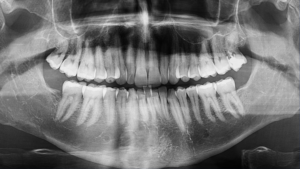

Raio-X Odontológico Panorâmico ou Periapical: Qual a Diferença e Quando Fazer?

Quando falamos sobre diagnóstico preciso na odontologia, o raio-X odontológico panorâmico ou periapical desempenha um papel essencial. Embora ambos tenham a mesma finalidade — auxiliar o dentista na avaliação da